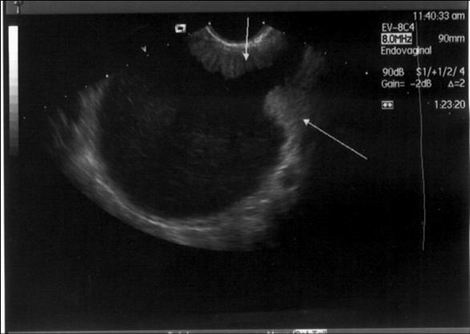

- Zobrazovací metody: US diagnostika Senzitivita: 87 %, specificita: 67 % Ferrazi,1997, grey scale US, Doppler US ( 0.4 RI: 100 % senz. 96-99% spec.), jiné zobrazovací metody (nemá lepší výsledky), MRI, CT, PET…

U nádorů LMP: (morfologie, flow, CA 125 )

- Alespoň jeden test abnormální: 93%

- 2 abnormální: 69 %

- 3 abnormální: 21 % Gotlieb 2000